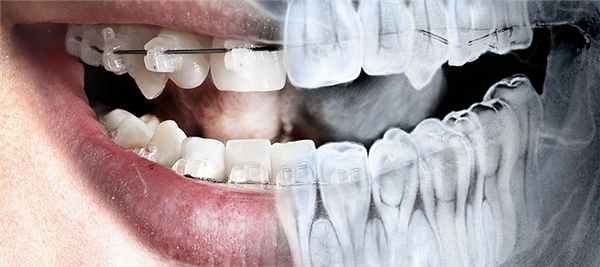

- Телерентгенограмма (ТРГ).

Телерентгенограмма (ТРГ)

Этот вид диагностики позволяет исследовать не только челюстную структуру, но и получить снимок всего черепа в фас и профиль. Относится к числу наиболее информативных диагностических процедур в стоматологии.

ТРГ проводится в обязательном порядке перед установкой брекет-систем, а также широко используется перед предстоящими операциями в качестве подготовительной меры.